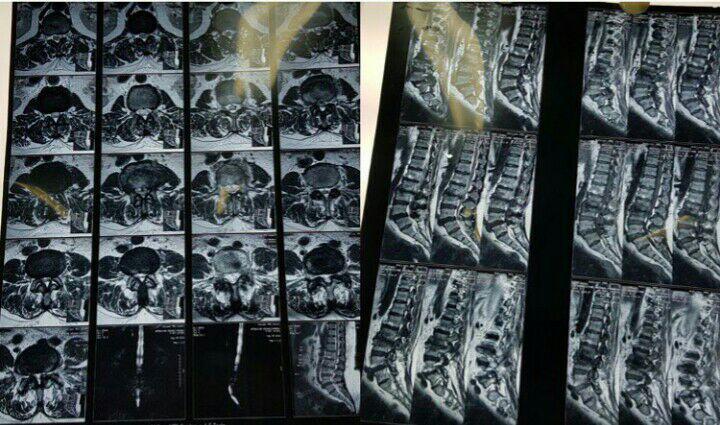

-لیزر(جراحی بسته) دیسک کمری

-درمان دردهای مزمن , ستون فقرات , سردردهای مزمن

-اوزون تراپی دیسک بین مهره ای

-درمان تنگی کانال نخاعی غیرقابل جراحی

متخصص درد با بررسی دقیق علائم بیمار و انجام معاینات فیزیکی و پاراکلینیکی، نوع درد (حاد، مزمن، عصبی، اسکلتی عضلانی و …) و علت آن را تشخیص میدهد.